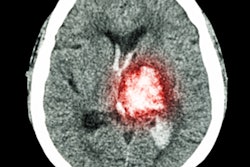

Can machine learning used with conebeam CT (CBCT) help clinicians predict whether patients who have experienced stroke will have peripheral bleeding after they've undergone thrombectomy? Perhaps, according to a team of Italian researchers.

The ability to predict peripheral bleeding (i.e., hemorrhagic transformation) after endovascular thrombectomy is crucial, as the complication can be deadly, wrote a group led by Dr. Valerio Da Ros of the University Hospital of Rome in a study published October 25 in Neuroradiology.

Stroke patients typically undergo a CBCT exam immediately after thrombectomy, then have a noncontrast CT 24 hours after that in order to detect any additional bleeding, guide an anticlotting regimen, and/or assess the final infarct volume. The ability to predict with CBCT whether a patient will have peripheral bleeding after the procedure would improve patient outcomes, but previous research on this has been focused on evaluating the efficacy of visual assessment of the CBCT images -- which, since reader interpretation is subject to variability, could affect its predictive performance. That's where machine learning could help.